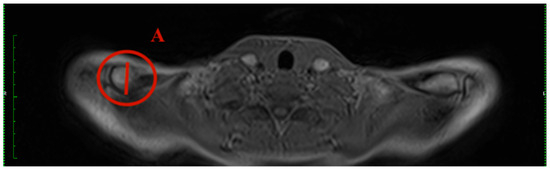

- Sternal angle: The sternal angle alpha was measured by the plug-in after the two tangents were drawn. Tangent 1 aligns at the sternal articular surface of the sternoclavicular joint, and tangent 2 is at the cranial end of the manubrium (Figure 1).